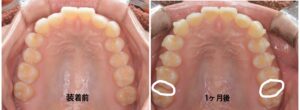

しかし、経過を記録するために口腔内写真を撮影してみると、歯の動きは一目瞭然でした。

なんと、IPR(歯のやすりがけ)をしていない一番奥の歯にまで隙間ができていたのです。1番奥の歯が遠心方向(奥側)に移動しており、自分でも驚くほど。

その瞬間、「これが痛みの原因だったんだ」と納得。